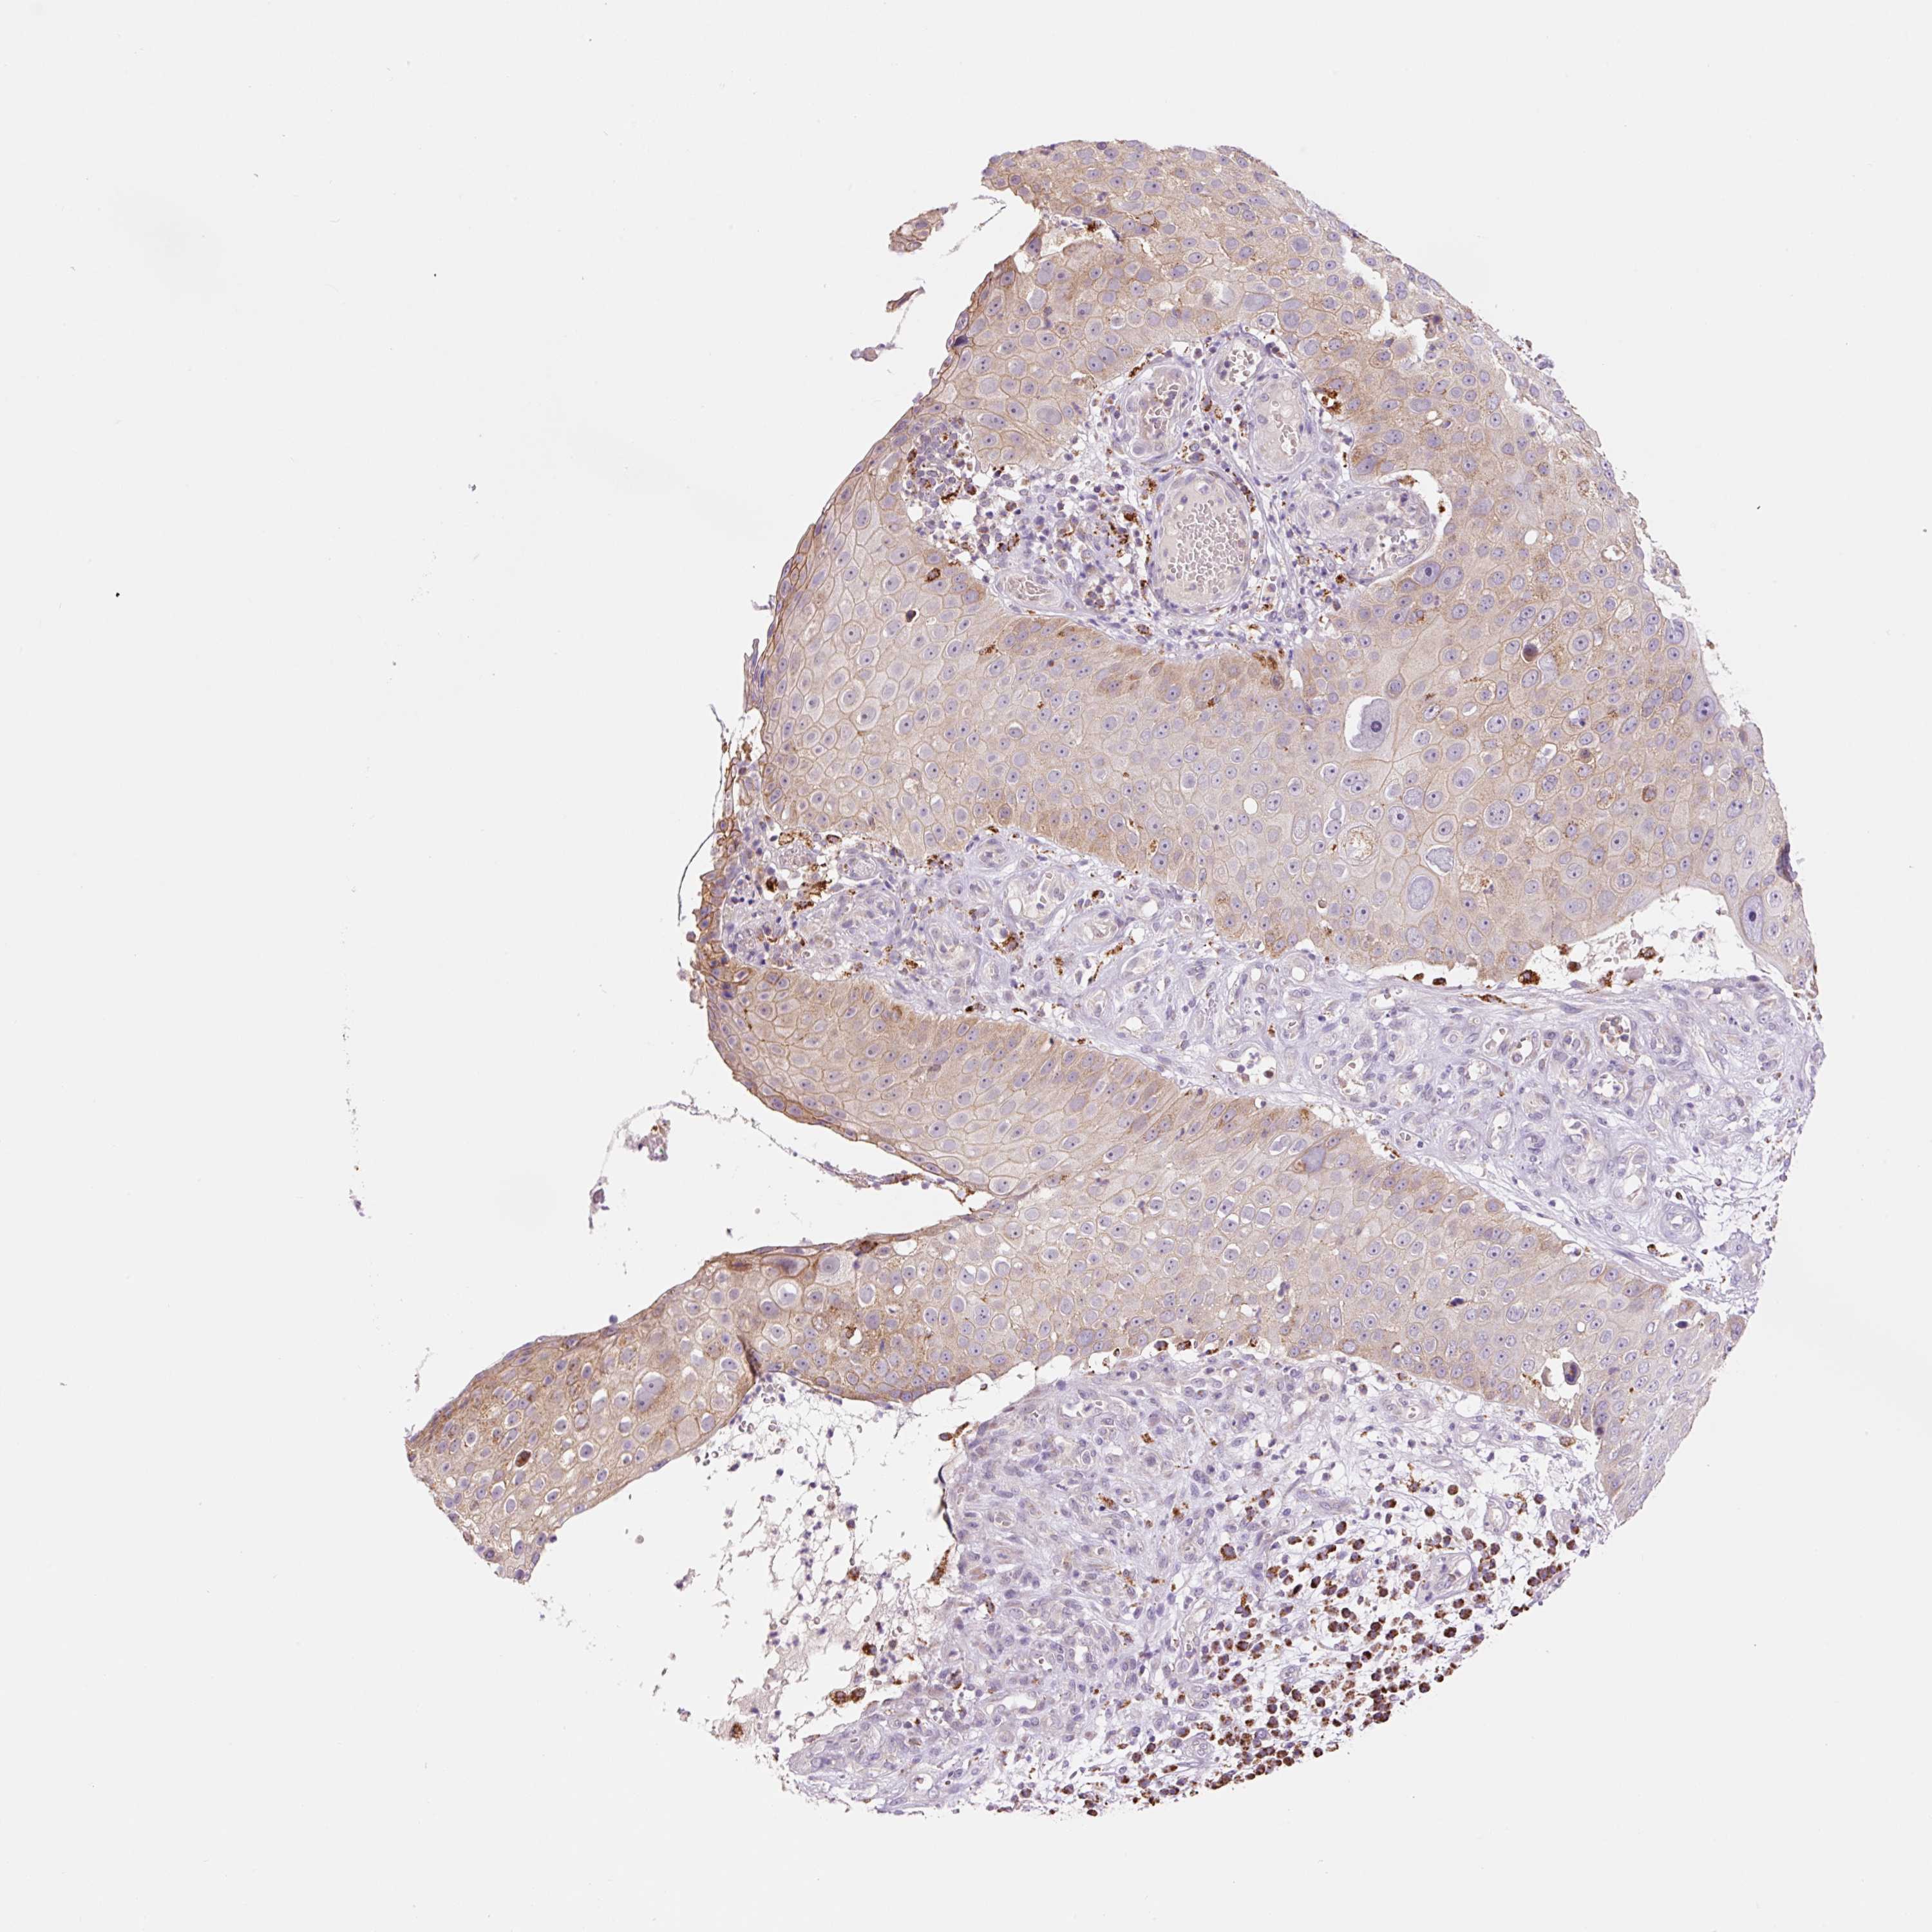

SKIN CANCER - Protein expressioni

A mouse-over function shows sample information and annotation data. Click on an image to view it in a full screen mode. Samples can be filtered based on level of antibody staining by selecting one or several of the following categories: high, medium, low and not detected. The assay and annotation is described here.

Each image is clickable and will lead to virtual microscopy that enables deeper exploration of all samples and also displays staining intensity scores, fraction scores and subcellular localization as well as patient and tissue information for each sample.

Antibody HPA053502

Staining

High

Medium

Low

Not detected

Intensity

Strong

Moderate

Weak

Negative

Quantity

>75%

75%-25%

<25%

None

Location

Nuclear

Cytoplasmic/membranous

Cytoplasmic/membranous,nuclear

Squamous cell carcinoma, NOS

Squamous cell carcinoma, metastatic, NOS

Squamous cell carcinoma in situ, NOS